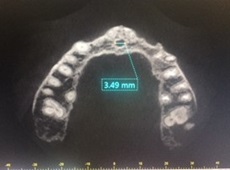

La primera medida perpendicular se obtuvo en el corte sagital oblicuo a nivel inferior del CNP situado desde la cortical interna hasta la cortical externa de su pared anterior. La segunda medida se obtuvo a nivel medio del mencionado conducto, equidistante entre la porción superior e inferior, situado desde la cortical interna y externa. La tercera medida se obtuvo a nivel superior de la pared anterior del CNP, a nivel del piso de fosas nasales y de cortical interna a cortical externa. La medida vertical se realizó desde la medida superior a la inferior horizontal en el centro de la luz del conducto (ver imagen 1 y 3). La medida transversal se obtuvo en un corte axial a nivel de un punto equidistante entre superior e inferior (ver imagen 2 y 4).

Se observan las medidas vertical y del diámetro superior, medio e inferir del CNP

fotografía autores

En los pacientes dentados el promedio del diámetro a nivel inferior es de 2,5mm, a nivel medio es de 1,75mm y superior es de 2,33mm. El promedio de la altura es de 10,68mm y el diámetro transversal es de 3,45mm (Tabla 1 y Gráfico 1). En los pacientes edéntulos el promedio del diámetro a nivel inferior es de 3,55mm, a nivel medio es de 2,55mm y superior es de 3,01mm. El promedio de la altura es de 7,9mm y el diámetro transversal es de 4,55mm (Tabla 2 y Gráfico 2).